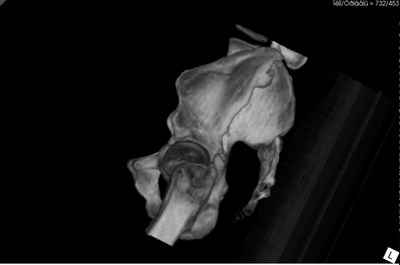

Добрый вечер уважаемые коллеги. Госпитализирован пациент с переломом таза 9-ти месячной давности (лечился где-то в районе консервативно). Помогите определиться с оптимальным вариантом хирургического доступа, фиксации.

Пациенту чуть больше сорока лет, работал в МЧС, после ДТП лечился по месту жительства консервативно. Жалобы пациента на постоянные боли в месте перелома, ощущение подвижности в месте перелома при ходьбе. Передвигается без дополнительной опоры, хромота не щадящая. Клинически отчетливо определяется патологическая подвижность крыла левой подвздошной кости. R-ммы не высылаю, сразу 3-D, если не хватит дошлю снимки.

Андрей, на 3d снимках не видно соотношение суставных поверхностей, величину диастаза в ложном суставе и состояние головки (может уже протез нужен).

Нужны стандартные снимки и срезы на уровне сустава и тела подвздошной кости.

Уважаемый Андрей!Исходя из данных КТ смещение не критичное (пациент ходит, головка "не истерлась и не рассосалась",беспокоит болево синдром.стабилизируйте поврежение из доступа,которым владеете лучше. в данном случае равноценны подвдошнопаховый и кохера-лангенбека с доплнительным окном по гребню. фиксация реконструкционными пластинами либо тазовыми винтами "Synthes".желаю успеха! Ушаков.